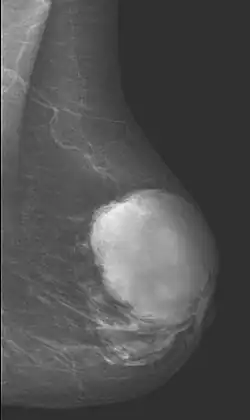

Diagnostic techniques

Radiographical imaging is the first-line test for identifying a phyllodes tumor.[11] Despite their propensity to grow rapidly and deform the overlying breast tissue, approximately 20% of phyllodes tumors can present as a nonpalpable mass on screening mammography.[12] Other imaging tools used to assess the size and spread of a phyllodes tumor include ultrasound and magnetic resonance imaging (MRI).[11] None of these imaging tools are definitive tests for differentiating a phyllodes tumor from a benign fibroadenoma.[13] Phyllodes tumors can only be diagnosed histologically, as they tend to have many overlapping features with other breast masses on physical examination and radiological imaging.[11]